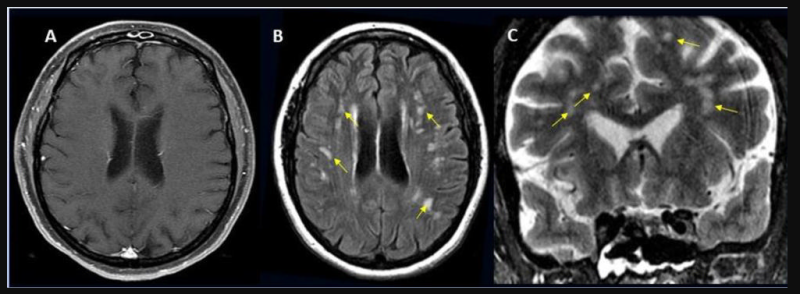

This photo gallery shows the variety of radiological presentations of COVID-19 (SARS-CoV-2) in medical imaging, including computed tomography (CT), radiograph X-rays, ultrasound, echocardiograms and magnetic resonance imaging (MRI). The radiology images show examples of typical COVID pneumonia in the lungs and the numerous complications the virus causes in the body in multiple organs, including the brain, kidneys, heart, abdomen and vascular system.